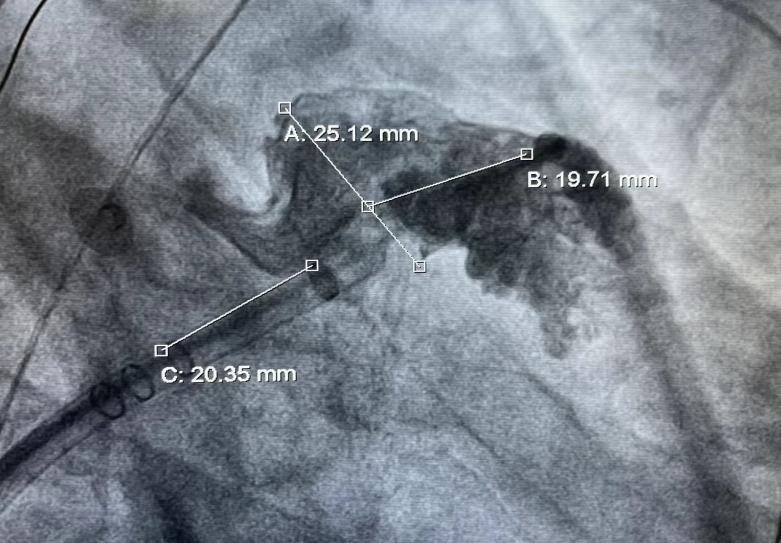

此例手术由韩稳琦博士和酉鹏华博士通过ICE指导下进行,通过ICE精准构建心脏模型、直视下穿刺房间隔,结合三维标测系统,精准、高效地完成双侧肺静脉隔离。后通过ICE及左心耳造影评估左心耳特征为下缘短,上缘折角大的短颈鸡翅型心耳,利用12F导引系统鞘管和猪尾导管在DSA肝位下同时造影,测量左心耳开口25.12mm,最大可用锚定区深度19.71mm,最终选择31mm规格watchman FLX封堵器的植入。ICE从不同角度检查即将释放的WATCHMAN FLX左心耳封堵器,观察封堵器位置、露肩、残余分流和压缩比情况,明确封堵器位置合理,无明显露肩,完全封堵无残余分流,封堵器位置良好。随后在ICE下观察及DSA透视下作牵拉试验,直到最后一次牵拉与前一次牵拉比较无位置改变,压缩比无明显变化,符合封堵器释放的“PASS”原则后完全释放封堵器。

图2 DSA测量左心耳开口及深度